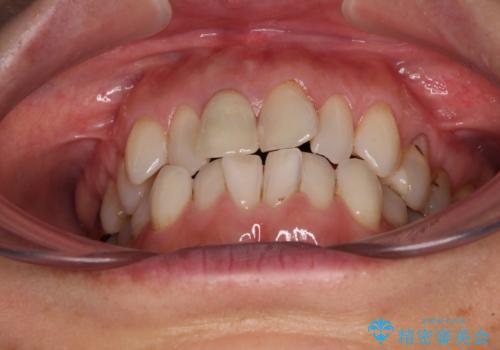

デコボコと銀歯 矯正治療とセラミック治療で綺麗な口元に

- 前歯のデコボコと口を開けたときに見える銀歯を気にして来院された患者様です。

ある程度デコボコが解消されれば大丈夫とのことで、インビザライン・モデレートパッケージを利用して歯列を整えて行くこととしました。

矯正治療後に銀歯をセラミッククラウンなどに置き換えていくと、どうしても後戻りを起こしてしまうため、矯正治療が概ね終了した時点で銀歯を全てセラミックとし、最後に仕上げでインビザラインにを用いて細かいデコボコを改善していくこととしました。

とても明るい口元となり、人目を気にせず、大きく口を開けて笑えるようになりました。